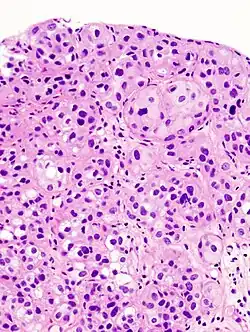

Rak urotelialny pęcherza moczowego, widoczne gniazda komórek nowotworowych

Mikroskopowo w utkaniu obecne są komórki tworzące gniazda, sznury komórek lub pojedyncze komórki pooddzielane desmoplastycznym podścieliskiem[76][78]. Możliwy jest bardziej rozlany wzór wzrostu nowotworu, w którym komórki tworzą arkusze, przy czym również w takim utkaniu spotyka się ogniskowo występujące gniazda komórek[78]. Komórki cechują się umiarkowaną do obfitej ilością amfofilnej lub eozynofilnej cytoplazmy i dużym hiperchromatycznym jądrem komórkowym. Jądra komórkowe wykazują znaczną pleomorficzność, nieregularne, kanciaste granice. Liczba i wygląd jąderek wykazuje znaczną zmienność. Gniazda komórek nowotworowych zwykle indukują reakcję desmoplastyczną podścieliska. Obecne są liczne figury mitotyczne i możliwa jest obecność nieprawidłowych figur mitotycznych. W podścielisku większości guzów jest obecny naciek limfocytów i komórek plazmatycznych, naciek najczęściej jest wyrażony ogniskowo od łagodnego do umiarkowanego stopnia, ale może być nasilony i rozlany[76][78]. Może być widoczna inwazja naczyń[78].